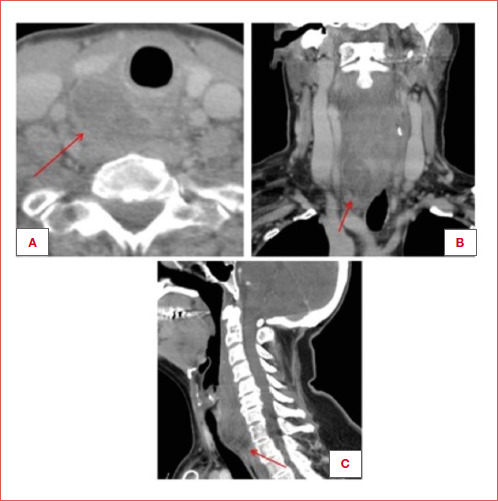

Conclusions: Parathyroid adenoma haemorrhage in middle-aged women with neck swelling, pain, and swallowing difficulty should be suspected. Diagnosis involves blood tests and contrast CT. Treatment is adenoma removal, typically without major complications.